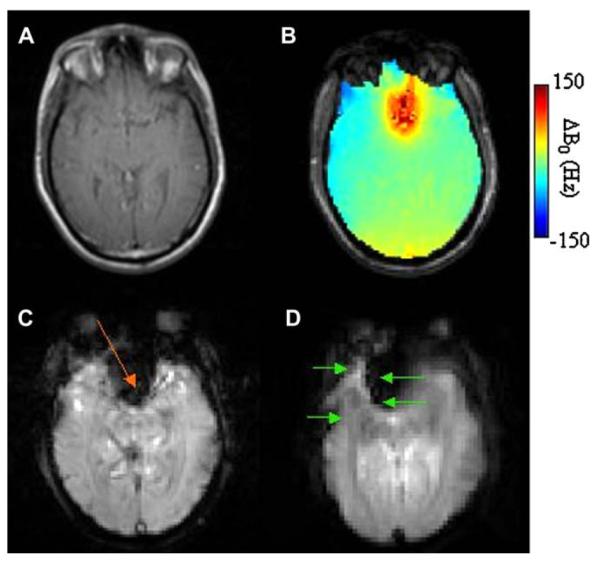

Fig. 1 shows (A) a fast-spin-echo (FSE) anatomic image of an axial slice (6 mm thick) through the frontal cortex of the human brain at B0 = 3T, (B) a ΔB0 field map over the same slice, (C) signal loss in weighted (TE = 35 ms) gradient-echo images (most prominent loss indicated with orange arrow), and (D) distortion in EPI images (indicated with green arrows), collected with TE = 25 ms, 64 × 64 in plane pixels over a 20 cm × 20 cm FOV, a readout bandwidth of 250 kHz. Arrows indicate directions of distortion in the phase-encoded dimension. The effects of B0 inhomogeneity on signal loss and EPI geometric distortion are clear.

Fig. 1.

(A) Fast-spin-echo (FSE) anatomic image of an axial slice (6 mm thick) through the frontal cortex of the human brain at B0 = 3T. (B) ΔB0 field map over the same slice, (C) signal loss in weighted (TE = 35 ms) gradient-echo images (most prominent loss indicated with orange arrow), and (D) distortion in EPI images (indicated with green arrows), collected with TE = 25 ms, 64 × 64 in plane pixels over a 20 cm ×20 cm FOV, a readout bandwidth of 250 kHz. Arrows indicate directions of distortion in the phase-encoded dimension.